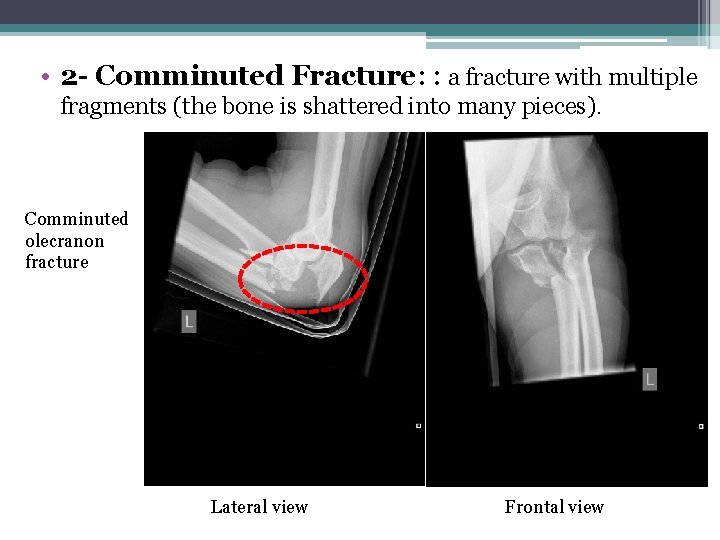

• 2 - Comminuted Fracture: : a fracture with multiple fragments (the bone is shattered into many pieces). Comminuted olecranon fracture Lateral view Frontal view